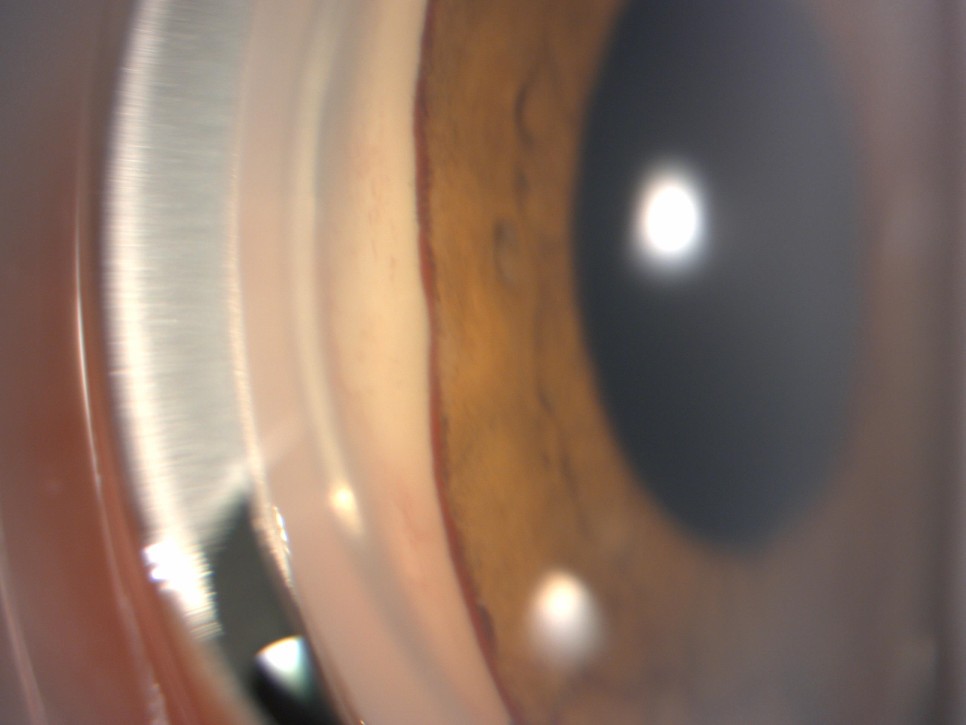

신생혈관 녹내장(NVG, neovascular glaucoma) 검사 결과 사진1. Anterior segment slit photography

홍채에 비정상적인 혈관이 보이고 맨몸에 섬유화가 진행된 부분도 보인다. 주름이 안쪽으로 말려 들어가 주름이 보이지 않는 부분도 있는데 이는 섬유화가 진행된 것과 마찬가지로 안압을 조절하는 기능을 거의 상실하였을 것이다.